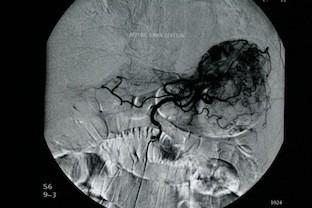

针对源自胃血管发育异常的大量上消化道出血进行选择性栓塞治疗。

Selective embolization for massive upper gastrointestinal bleeding deriving from gastric angiodysplasia.

Transcatheter arterial embolization is a valuable, minimally invasive method, used as treatment for upper gastrointestinal bleeding, after failed primary endoscopic approach. It is a safe and effective procedure, but it's use is limited because of relatively high rates of rebleeding and mortality. The aim of this paper is to present a case of severe, massive upper gastrointestinal bleeding deriving from gastric angiodysplasia, which was treated successfully with superselective embolization. The patient recovered from the haemorrhagic shock and avoided emergency surgical intervention.

经导管动脉栓塞术是一种有价值的微创方法,用于在初次内镜治疗失败后治疗上消化道出血。它是一种安全有效的手术,但由于再出血和死亡率相对较高,其应用受到限制。本文的目的是介绍一例因胃血管发育异常导致的严重大量上消化道出血病例,该病例通过超选择性栓塞术成功治疗。患者从失血性休克中康复,避免了紧急手术干预。